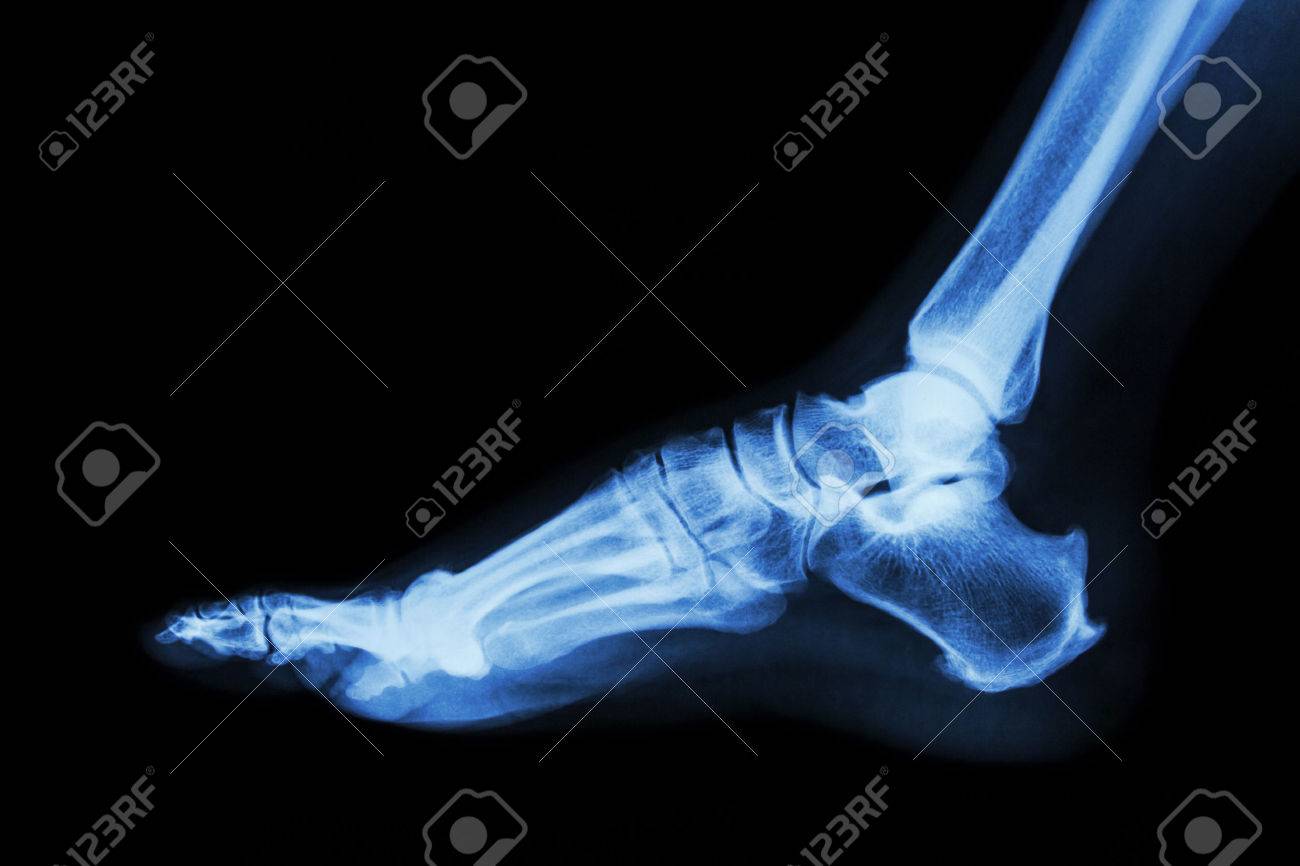

· Ham Clock looks great and is a real enrichment for every ham radio operator · RADIOGRAPHIE DE LA HANCHE DE FACE 4 juin 17 Dans "BANQUES D'IMAGES" RADIOGRAPHIE DU POIGNET DE FACE 4 juin 17 Dans "BANQUES D'IMAGES" Publié dans BANQUES D'IMAGES , Non classé , RADIOGRAPHIES Navigation des articles1) des radios en position debout FACE et PROFIL du pied EN ENTIER Elles permettent de mesurer les angles qui confirment la déformation en pied plat Le cliché de profil debout cherche à évaluer la divergence du talus et du calcaneum (ou inclinaison de l'astagale par rapport au calcaneum)

En effet, le pied étant un organe de la locomotricité (marche), l'analyse n'a d'intérêt que lorsqu'il est en appui Une radiographie du pied en charge nous permettra d'analyser précisément l'architecture de votre pied dans le cadre du bilan radiologiqueSearch query Yahoo Help;2,371 Free images of Radio Related Images microphone music sound audio retro technology headphones fireworks vintage radio 312 55 Radio Cassette Speaker 718 134 Car Traffic Man Hurry 409 63 Microphone Music Sound 310 90 Open Fire Fire Embers 131 162 Headphones Radio Music 167 31 Shower Of Sparks Light 130

· Les radiologues de centre d'imagerie IMBM, situé dans le quartier Batignolles Montmartre, dans le 18ème, réalisent votre radio de la cheville ou des pieds à ParisCet examen est réalisé en cas de douleurs, de traumatisme, de chute, de suspicion d'arthrose Nous réalisons les clichés conventionnels debout, de face, profil, avec les clichés en charge afin de réaliser lesPour une étude statique de vos pieds, les radiographies se réalisent debout, le pied sur le capteur Le profil de pied se réalise sur un marchepied spécifique Il vous faudra monter 3 marches et placer vos pieds de part et d'autre d'une gouttière où sera placé le capteur WIFI · Pour prendre une photo en projection directe (plantaire arrière) le pied est placé sur la semelle en position couchée, les jambes pliées au niveau des genoux Une image de chaque doigt sur le côté est réalisée avec la pose latérale du pied et

Passez une radio du pied Une fois à l'hôpital ou au cabinet du médecin, celuici va vous faire passer une série d'examens et de tests qui vont probablement inclure une radio des os du pied La radio permettra de savoir si l'os est gravement cassé ou s'il y a seulement une fracture de fatigue ou même s'il n'y a pas de fracture du toutGoogle Images The most comprehensive image search on the web · Digital radiography of the feet is performed at a clinic This technique creates a medical image using Xrays to view the foot's bone and joint structure With just one visit, digital imaging allows the podiatrist to make a rapid and accurate diagnosis of any issues affecting the feet Make an appointment Search for a clinic See all treatments